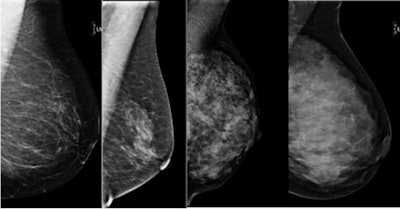

In fact, fewer than 10% of all women have "extremely dense" breast tissue, which is associated with twice the risk (relative risk of 2) of breast cancer as compared to women with average breast density. Some 40% of women have "heterogeneously dense" breast tissue, which is associated with a relative risk of approximately 1.2, according to Ojeda-Fournier.